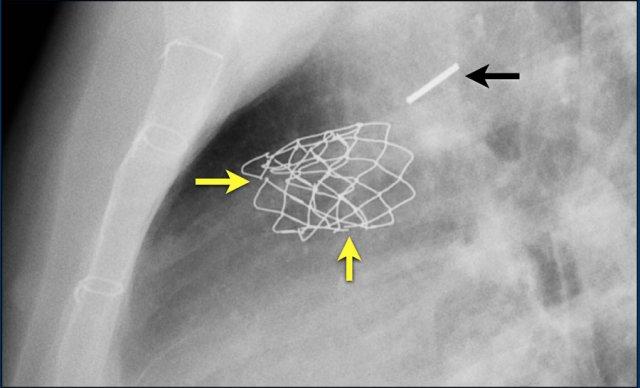

Stent Melody này có nhiều vị trí gãy (mũi tên vàng)